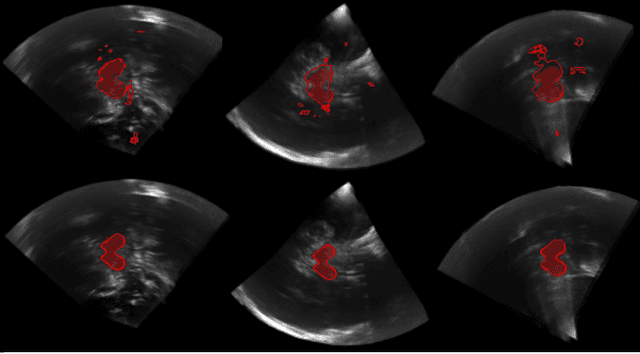

Abstract:In this work we propose a novel approach to perform segmentation by leveraging the abstraction capabilities of convolutional neural networks (CNNs). Our method is based on Hough voting, a strategy that allows for fully automatic localisation and segmentation of the anatomies of interest. This approach does not only use the CNN classification outcomes, but it also implements voting by exploiting the features produced by the deepest portion of the network. We show that this learning-based segmentation method is robust, multi-region, flexible and can be easily adapted to different modalities. In the attempt to show the capabilities and the behaviour of CNNs when they are applied to medical image analysis, we perform a systematic study of the performances of six different network architectures, conceived according to state-of-the-art criteria, in various situations. We evaluate the impact of both different amount of training data and different data dimensionality (2D, 2.5D and 3D) on the final results. We show results on both MRI and transcranial US volumes depicting respectively 26 regions of the basal ganglia and the midbrain.